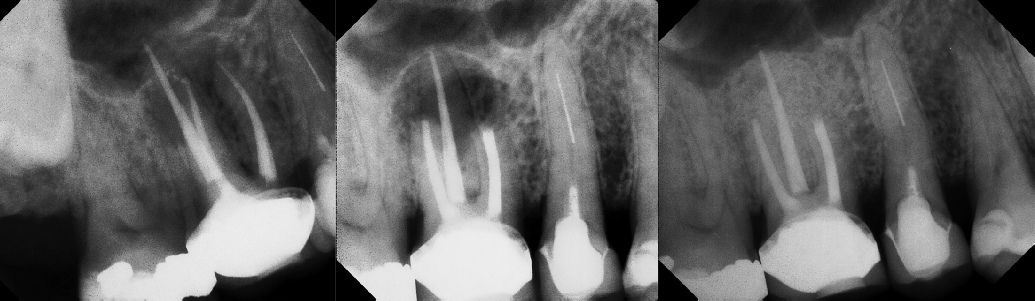

COMPLICATED ANATOMY LARGE LESIONS CALCIFIED CANALS PERFORATION / RESORPTION SEPARATED INSTRUMENTS SURGICAL CASES RETREATMENT / pOST REMOVAL OPEN APICES ACCESS THRU CROWNS Root Canal Case Portfolio

Apicoectomy - Surgical Root Canal Pre-op (post trauma) Coronal segments obturated Apical segments surgically removed 3 years